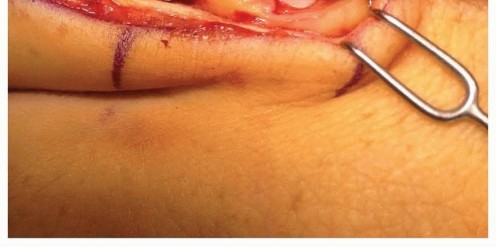

When closed reduction fails, or for complex, comminuted, or multiple metacarpal fractures, Open Reduction and Internal Fixation (ORIF) is mandated. A dorsal longitudinal or slightly gently curved incision is made centered over the fractured metacarpal. Careful subcutaneous dissection is performed to identify and meticulously retract the dorsal sensory nerve branches using vessel loops. The extensor apparatus is exposed. Depending on the fracture location, the extensor tendon can be retracted laterally, or the extensor mechanism can be split longitudinally (e.g., splitting the EDC tendon) to access the dorsal periosteum.

Periosteal elevation must be judicious and strictly limited to the footprint required for plate application. Circumferential stripping of the periosteum is a catastrophic error that devascularizes the bone fragments and invites nonunion. The fracture site is gently debrided of hematoma and interposed soft tissue. Anatomical reduction is achieved using specialized reduction forceps, taking immense care to avoid crushing fragile cortical edges. Provisional fixation is maintained with fine (0.035-inch or 0.045-inch) K-wires.

Clinical & Radiographic Imaging Archive